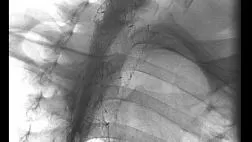

Через три недели больным проводилась дилатация глоточно-пищеводного перехода по вышеописанной методике. Перед повторной дилатацией больным проводилось рентгеноконтрастное исследование, на котором определялся дивертикул меньших размеров, чем до начала лечения. Опорожнение дивертикула проходило быстро. Наложение рентгенограмм с совмещением костных структур до и после введения препарата «Диспорт» в крикофарингеальную мышцу представлено на рисунке 41.

На рисунке представлены два снимка больного дивертикулом Ценкера. Снимки наложены друг на друга с совмещением костных структур. Первый снимок выполнен до проведения больному эндоскопической баллонной дилатации с введением препарата «Диспорт» в область крикофарингеальной мышцы. Второй сделан спустя три недели после проведения манипуляции. На рисунке видно, что дивертикул значительно уменьшился в размере, явления дисфагии регрессировали.

За двумя больными ведётся наблюдение в течение 6 лет, прогрессирование симптомов характерных для дивертикула Ценкера не наблюдается.